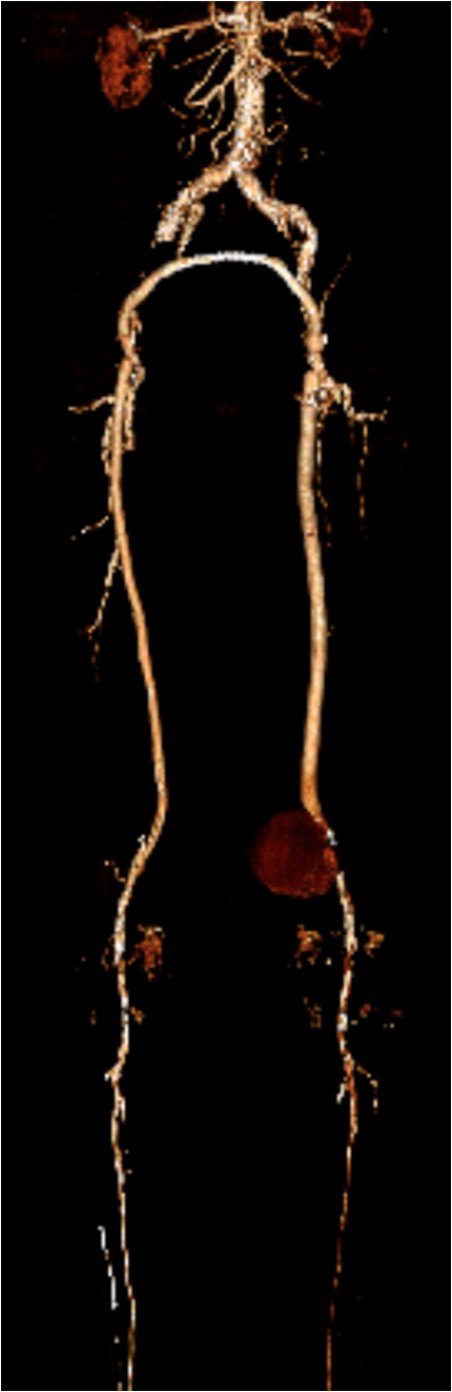

Coronal view of popliteal PS of distal anastomosis site of femoral–popliteal bypass.

Popliteal PA following revascularization is a rare occurrence and may present many years later. They range in their presentation from asymptomatic pulsatile mass to acute rupture with hemorrhage. The identification and resolution of these lesions are aided by advanced imaging techniques, proper operative planning and patient-specific treatment options. In patients with multiple comorbidities, deemed high risk for cardiac events during surgery, an endovascular approach is a safe and viable option. We describe the successful treatment of a large PA at the distal anastomosis of a femoral–popliteal bypass graft using an 11 × 10 mm Viabahn stent with subsequent aspiration of the PA.